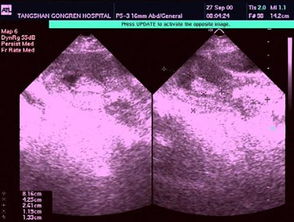

5、7天后是否要到醫院去復查B超?

大夫沒(méi)告你啊,做完刮宮的一周后要檢查的啊